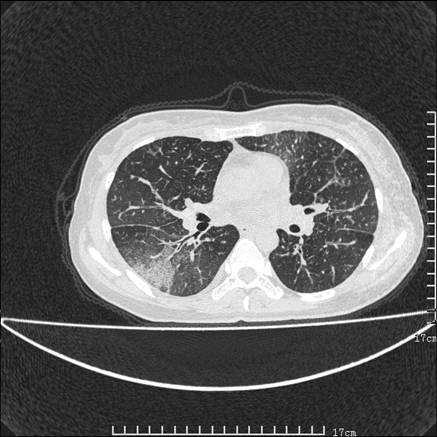

女,46岁,患胃溃疡多年,溃疡大小约1.0cm左右,后于5年前手术,病理为胃癌。主诉:半月前感冒后胸闷,气短,有咳嗽,无明显咳痰,无发热。偶有腰背部不适。

以下为高分辨扫描图像

双肺小叶间增厚,双肺散布粟米影和磨玻璃状影,以双肺上叶为重。结合病史考虑转移(癌性淋巴细管炎)可能性大。

结合病史:认为是典型肺部癌性淋巴管炎、淋巴结转移。请看图解。

正如caihe主任所言,影像表现结合临床病史应该支持肺癌性淋巴管炎;上肺大片边缘不清的渗出病变,多系感染所致,临床有感冒病史并咳嗽表现。肺癌性淋巴管炎临床一般无咳嗽、咳痰症状。

肺癌性淋巴管炎征象分为主要征象及合并征象,主要征象包括:

1、近肺门支气管血管周围间质结节状增厚;

2、小叶间隔结节状增厚;

3、小叶中央间质结节状增厚;

4、胸膜下间质结节状增厚。

合并征象为:纵隔淋巴结增大,胸腔积液,肺多发随机分布的小结节等。